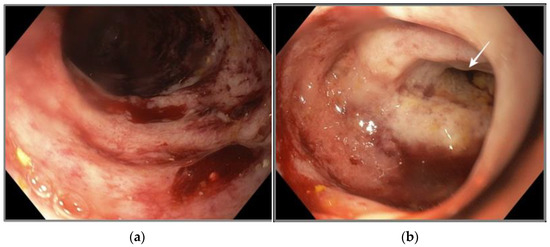

2.4. Gastric and Duodenal Histology